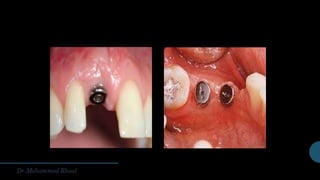

ONE-STAGE IMPLANT PLACEMENT

When aesthetics are not of concern, the cover screw or healing cap of the dental implant may be left exposed

during healing process and osseointegration period .

though several prerequisites must guide proper patient selection for this approach:

•The patient must have bone quality (ideally type I or II) and quantity sufficient to ensure primary stabilization

(the initial engagement between the bone and implant), i.e., no GBR required.The ISQ system is essential to

confirm stability in this instance.

• An adequate circumferential zone of keratinized gingival tissue must be present.

•The abutment must precisely fit the implant.

•The abutment must be tightened to the proper torque value as dictated by the implant manufacturer.Torque

values are measured in N/cm and are different for each dental implant system. Using the proper torque value

is critical in order to prevent undue loosening.

• Abutment height must not compromise occlusion, and absolutely no contact or loading with the opposing

dentition.